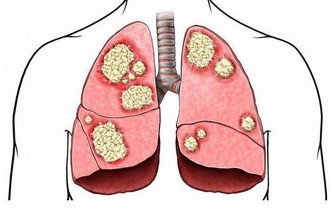

*****8.低密度脂蛋白膽固醇也不能過低。*****

儘管低密度脂蛋白膽固醇的含量較低,通常意味著一個人較為健康,但一項新的臨床資料顯示,一些癌症患者體內的低密度脂蛋白膽固醇含量也非常低。研究發現,血液中低密度脂蛋白膽固醇含量過低的人容易出現各種感染,被感染的持續時間較長,可能誘發癌症。